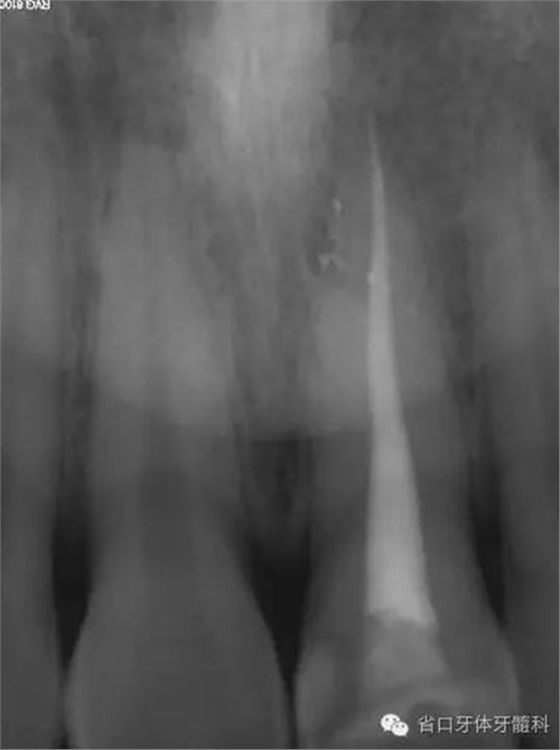

術(shù)前X線片

X線片示21冠折,根段未見明顯牙折影像。

根充后X線片